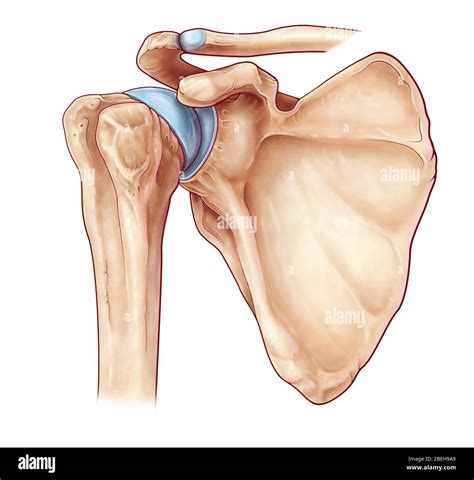

The greater tubercle of humerus is situated on the lateral aspect of the humeral head, adjacent to the articular surface. It is one of two key projections at the top of the humerus, the other being the lesser tubercle, which sits anteriorly. Separating these two structures is the bicipital groove, also known as the intertubercular sulcus, which houses the long head of the biceps brachii tendon.

The surface of the greater tubercle is distinctively roughened, providing an optimized surface area for the insertion of three of the four rotator cuff muscles. This anatomical positioning is not accidental; it provides the mechanical advantage necessary for the shoulder joint to execute movements like abduction and external rotation. The specific arrangement of these muscle attachments is described below:

• Supraspinatus: Attaches to the superior facet of the greater tubercle.

• Infraspinatus: Attaches to the middle facet.

• Teres Minor: Attaches to the inferior facet.